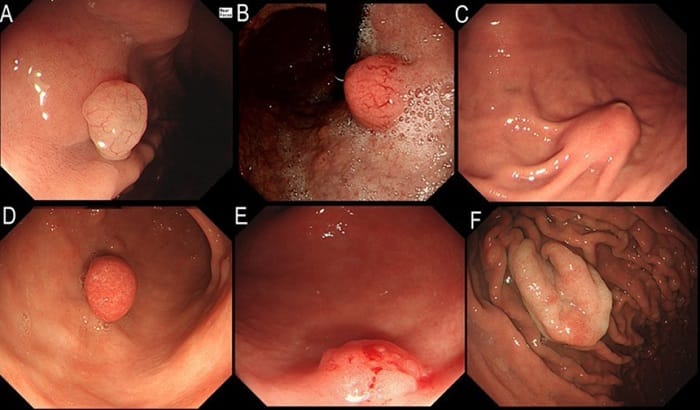

Tùy thuộc vào vị trí, kích thước polyp mà thời gian lành khác nhau

Tùy vào từng vị trí polyp mà sẽ có thời gian lành khác nhau:

- Polyp dạ dày: Polyp nhỏ liền vết sẹo sau 1–2 tuần. Polyp lớn cần khoảng 3–4 tuần để niêm mạc hồi phục hoàn toàn. Thời gian dài hơn ở polyp lớn do diện cắt rộng hơn, niêm mạc phải tái tạo và lành sẹo.

- Polyp đại tràng: Polyp nhỏ liền trong khoảng 1 tuần. Polyp lớn hoặc nhiều polyp vòng cắt rời đi trong 5–7 ngày, niêm mạc đại tràng ổn định hoàn toàn sau vài tuần. Việc hồi phục lâu hơn do vùng cắt rộng và nhu động ruột liên tục tác động lên vết thương.